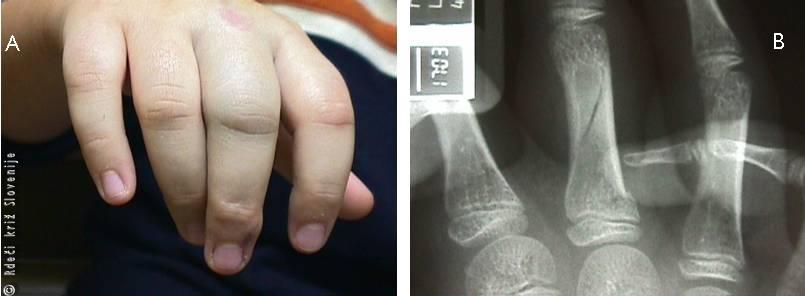

Slika 23

A – Oteklina, spremenjena oblika s križanjem prstov pri upogibu po zlomu bližnjega členka.

B – Rentgenska slika spiralnega zloma telesa in baze bližnjega členka. Gre za zlom pri otroku, saj so še prisotne rastne stike.

Oteklina, spremenjena oblika s križanjem prstov pri upogibu po zlomu bližnjega členka.